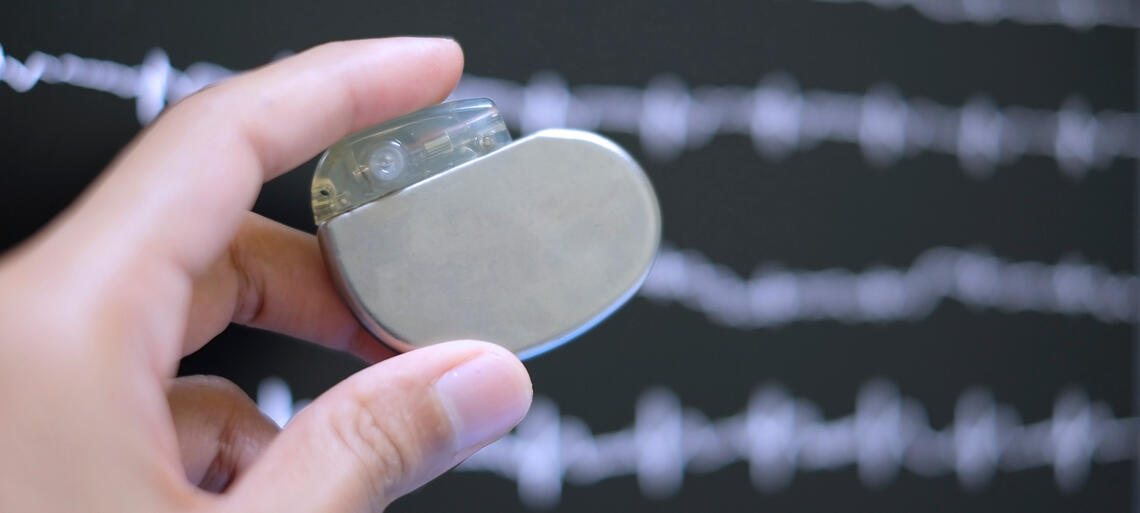

Il pacemaker: tecnica tradizionale o senza fili?

Esistono diverse tipologie di pacemaker: leggiamo nel dettaglio le indicazioni e le limitazioni di ogni tecnica di impianto.

A cosa serve il pacemaker?

L'applicazione di un pacemaker permette di correggere i disturbi dell’attività del cuore legati ad anomalie del ritmo nel caso in cui vi sia il rallentamento patologico della frequenza del battito cardiaco.

Il pacemaker viene impiantato per evitare i disturbi legati alla bassa frequenza cardiaca (stanchezza, vertigini o svenimenti) o per eliminare il rischio di arresto cardiaco.

I pacemaker moderni rilevano inoltre dati importanti sulla salute del paziente, che vengono valutati dal medico specialista, anche con il sistema di telemedicina.